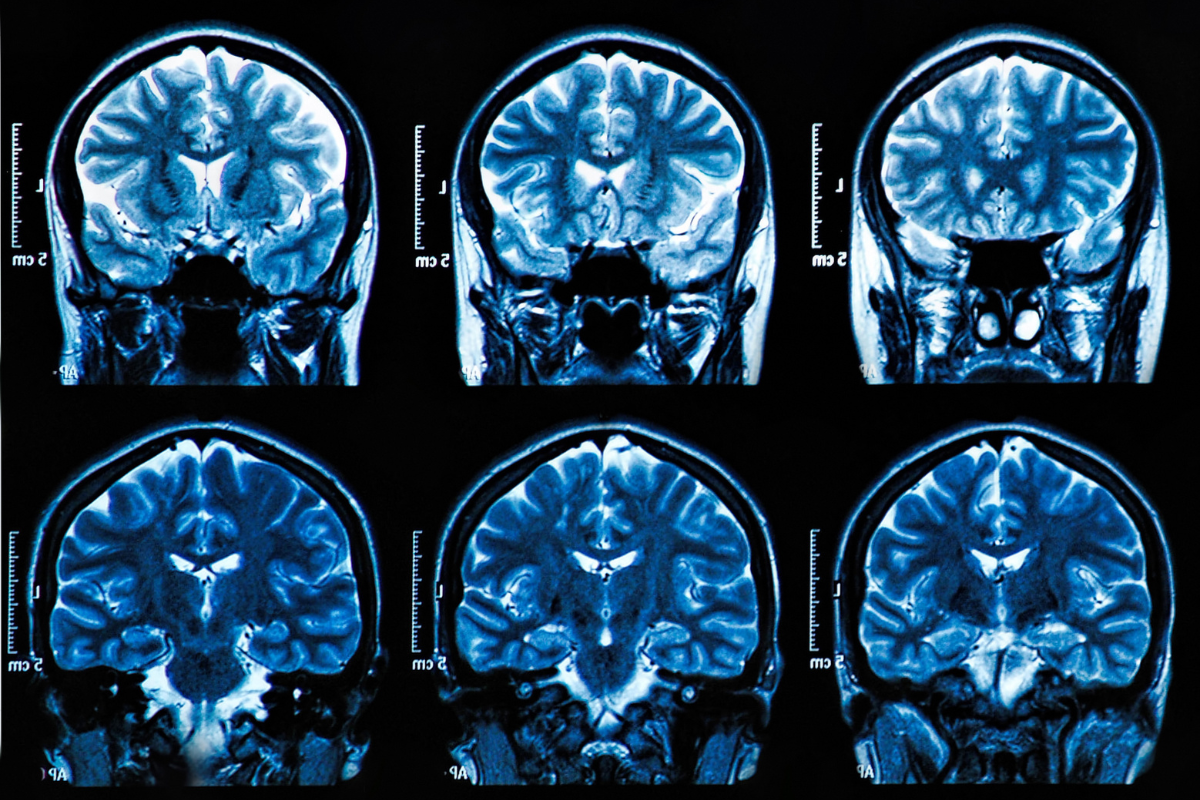

MS and Parasites Cause Brain Lesions

Revealing the Overlooked Link Between Parasitic Infections and Multiple Sclerosis A New Perspective on Multiple Sclerosis For decades, people diagnosed with multiple sclerosis (MS) have been told that their immune system is attacking their body for no reason — that it’s an autoimmune disease with no known cause and no cure. But new research tells